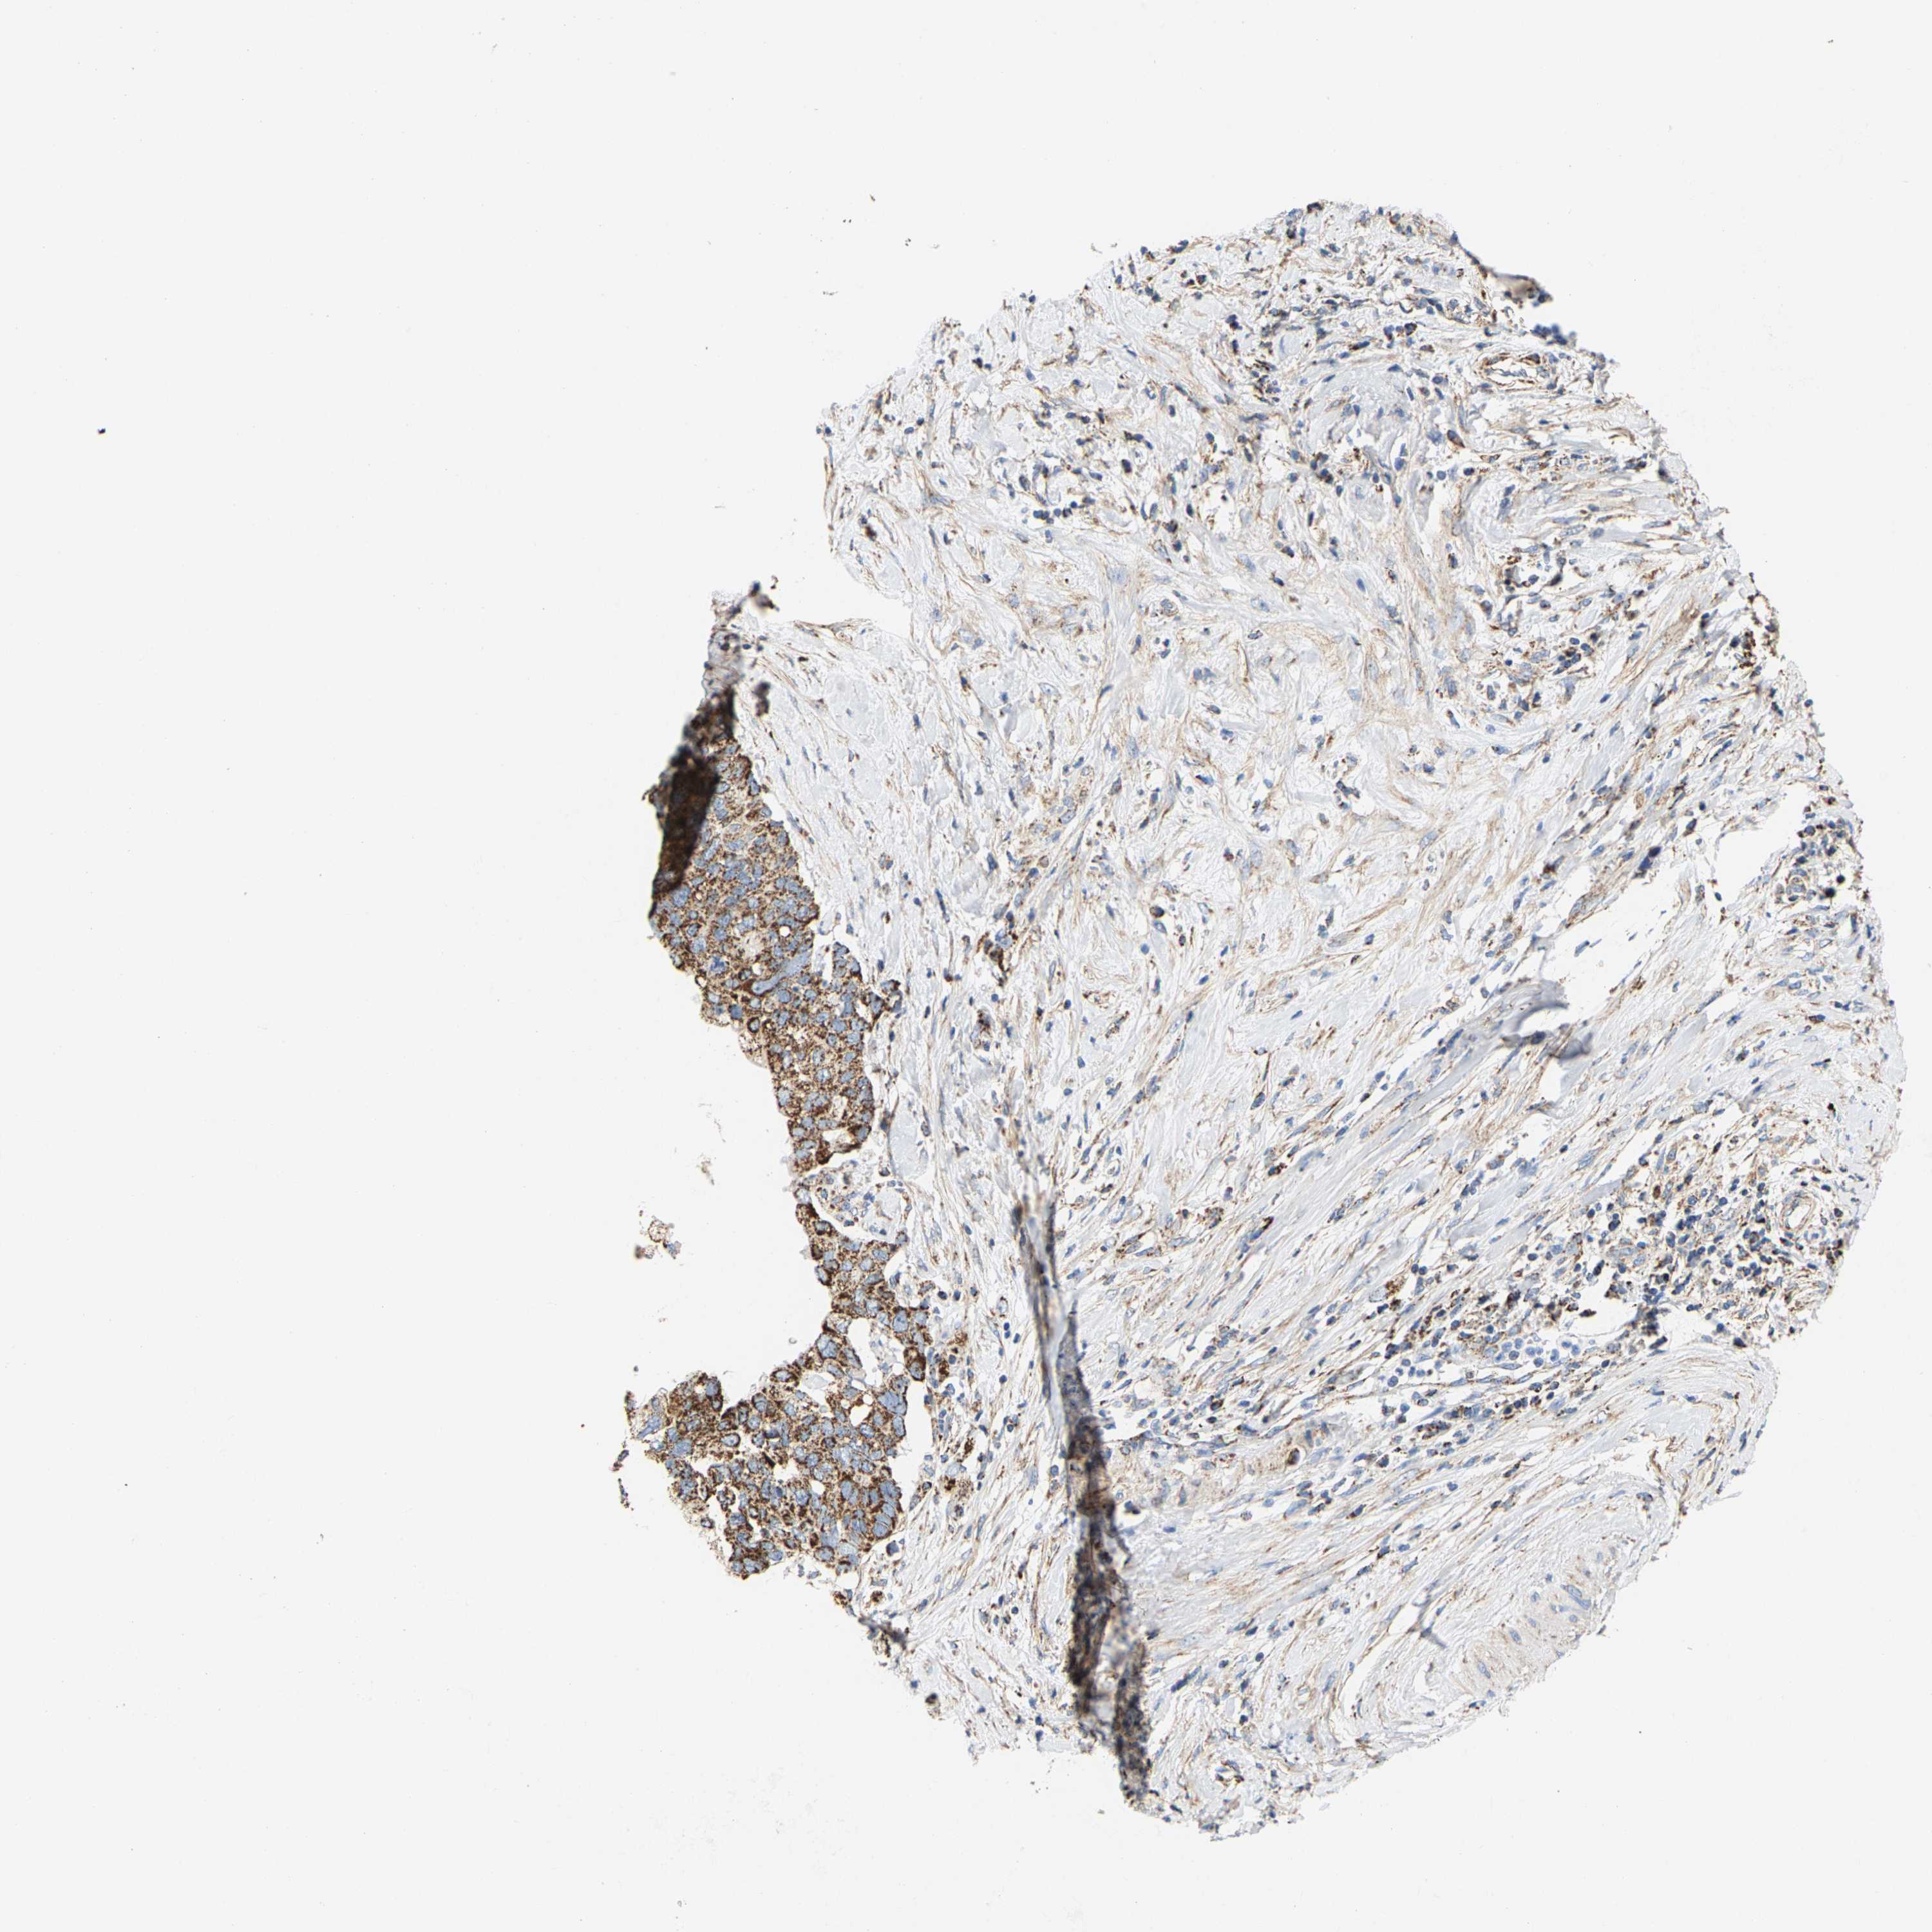

PANCREATIC CANCER - Protein expressioni

A mouse-over function shows sample information and annotation data. Click on an image to view it in a full screen mode. Samples can be filtered based on level of antibody staining by selecting one or several of the following categories: high, medium, low and not detected. The assay and annotation is described here.

Note that samples used for immunohistochemistry by the Human Protein Atlas do not correspond to samples in the TCGA dataset.

Antibody stainingi

Antibody staining in the annotated cell types in the current human tissue is reported as not detected, low, medium, or high, based on conventional immunohistochemistry profiling in selected tissues. This score is based on the combination of the staining intensity and fraction of stained cells.

Each image is clickable and will lead to virtual microscopy that enables deeper exploration of all samples and also displays staining intensity scores, fraction scores and subcellular localization as well as patient and tissue information for each sample.

Antibody HPA020543

Antibody HPA020549

Staining

High

Medium

Low

Not detected

Intensity

Strong

Moderate

Weak

Negative

Quantity

>75%

75%-25%

<25%

None

Location

Nuclear

Cytoplasmic/membranous

Cytoplasmic/membranous,nuclear

Adenocarcinoma, NOS